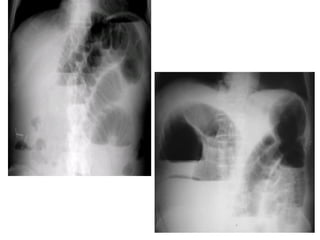

THUÛNG TAÏNG ROÃNG

* Daáu hieäu kinh ñieån: lieàm hôi döôùi hoaønh: xuaát hieän 6-8

giôø sau thuûng vôùi löôïng hôi khoaûng 20-50ml

* Caùc tö theá khaùc: BN nghieâng (T) laáy heát bôø ngoaøi gan vaø

oThủng vào khoang sau phúc mạc

o Thủng vào hậu cung mạc nối với lỗ Winslow bị bít

o Thủng phần cao ống tiêu hoá được phúc mạc bít

oLỗ thủng bị bít do giả mạc hoặc do niêm mạc phù nề

 Vài trường hợp đặc biệt của thủng tạng

rỗng

oThủng vào hệ mật

oThủng vào hậu cung mạc nối

oThnủng vào khoang sau phúc mạc

Thủng tạng rỗng không thấy liềm hơi

dưới hoành

Chẩn đoán phân biệt liềm hơi dưới hoành:

-Túi hơi dạ dày

-Mô phổi bình thường nằm giữa đáy phổi và cung sườn sát

trên với đáy phổi

-Hội chứng Chilaiditi